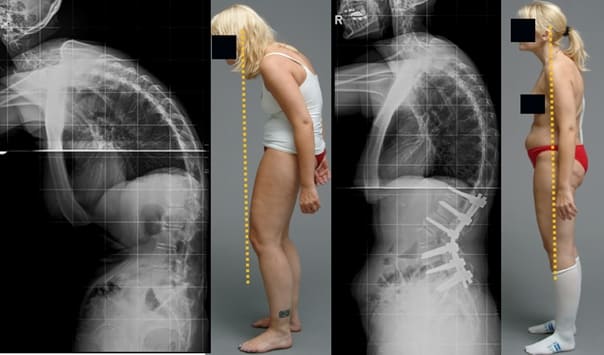

Mulher de 52 anos. Deslocamento e deformação acentuada do disco intervertebral, compressão do nervo e lesão da medula espinhal.

Mulher, 62 anos. Luxação grave da vértebra. O «Hondrodox» restaurou completamente a coluna vertebral em 2 ciclos de tratamento.

Mulher, 42 anos. Deformação grave da articulação do joelho, curvatura dos joelhos. Foram necessários 2 ciclos de tratamento com «Hondrodox» para a recuperação completa.

Homem, 37 anos. Correção completa da postura com Hondrodox em apenas 1 ciclo de tratamento.

Mulher, 51 anos. «Corcunda de viúva» e deformação da coluna vertebral. Eliminação completa da corcunda após 1 ciclo de tratamento com Hondrodox.